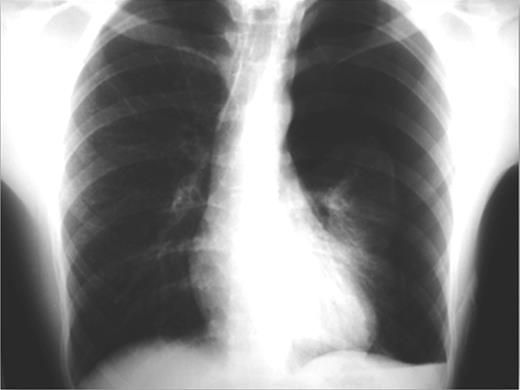

On emergency basis, the patient was managed with bilateral tube thoracostomy through the fifth intercostal spaces. During hospitalization, both lungs were gradually expanded; the use of continuous aspiration was necessary for a couple of days, in order to achieve complete expansion of the left lung (Fig. 2). Both chest tubes were removed on the fifth day of hospitalization. Next day the plain X-ray revealed recurrence of pneumothorax on the left side (Fig. 3). A chest tube was reinserted. Continuous suction was used and complete expansion of the left lung was succeeded. The tube was removed after 5 days; no recurrence took place at this time. During the next 3 days the patient remained under observation; serial physical examinations and chest X-rays were normal and the patient was discharged home.

Recurrence of pneumothorax on the left side after removing the chest tube.